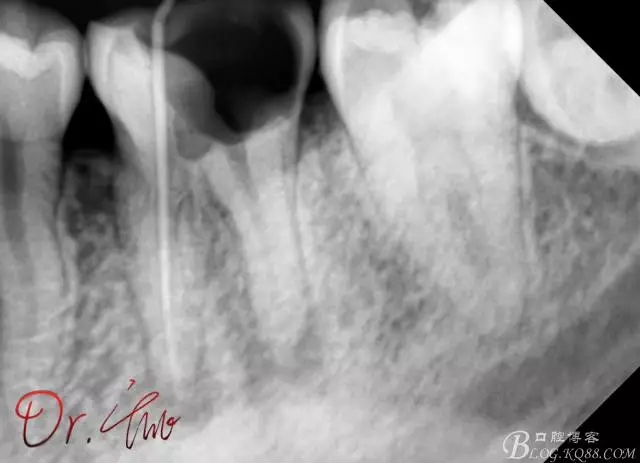

初診照

640.webp.jpg